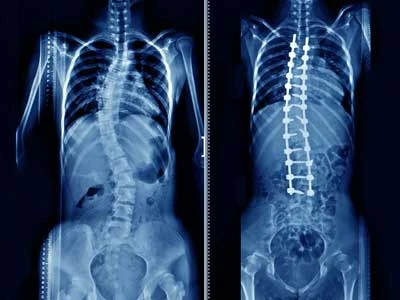

Surgical correction of spinal curvature abnormalities

Comprehensive spinal realignment procedures